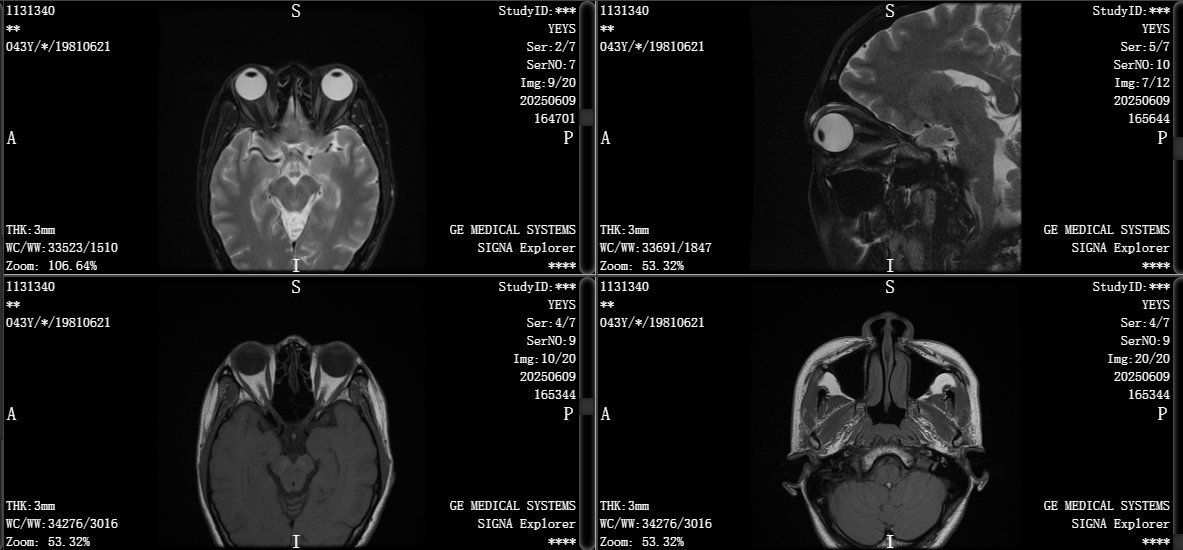

4-3 眼部MRI